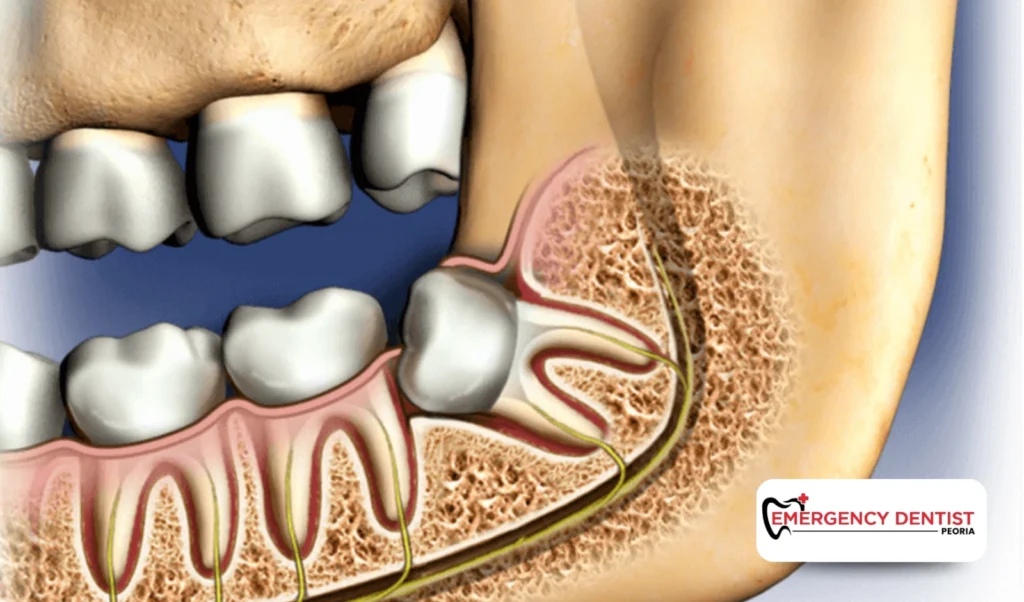

A surgical extraction is needed when the tooth is impacted, broken, or positioned below the gums. This approach may involve adjusting gum tissue or dividing the tooth, which can affect wisdom teeth removal cost.

An impacted wisdom tooth does not fully break through the gums. This can lead to pressure, swelling, or infection. Removing impacted teeth often requires oral surgery techniques and careful planning.

Because of the added steps involved, impacted cases often influence the average cost of a wisdom tooth removal more than straightforward extractions.